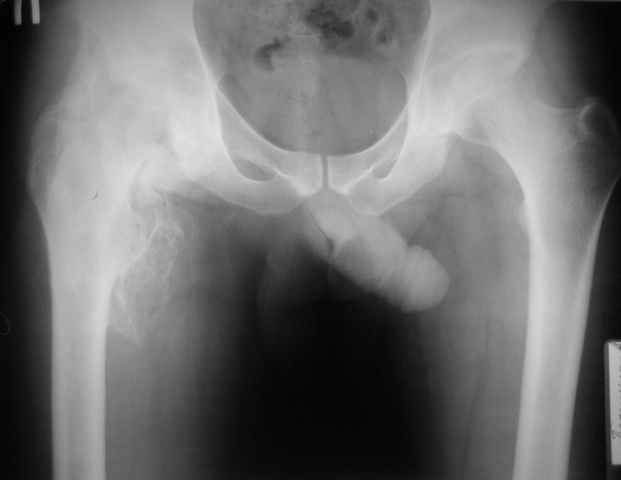

Уважаемые коллеги, здравствуйте! Пациент 1987 года рождения, сочетанная травма (ЗЧМТ,

перелом костей голени) в январе 2010 года.

Около месяца на ИВЛ, В настоящее время неврологически компенсирован, ходит с ходунками,

адекватен. Основная жалоба - отсутствие движений в тазробедренном суставе. Клинически

наружная ротация 30 гр. умеренная мышечная атрофия, движения качательные.

Рентгенологически-выраженные гетеротопические оссификаты в области правого

тазобедренного сустава. Помогите определитсья с тактикой:Эндопротезирование? Сроки?